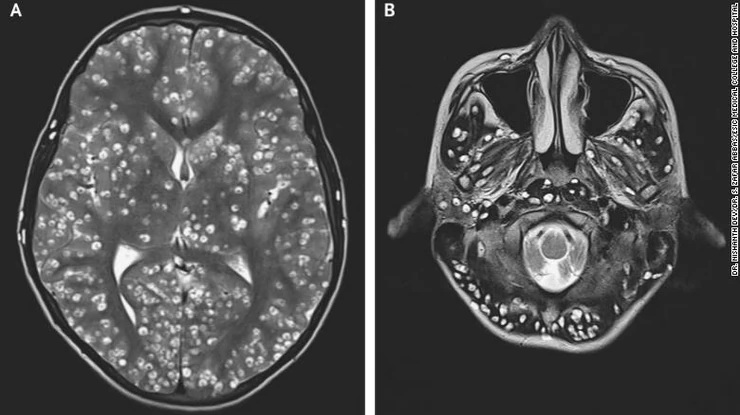

Roditelji tinejdžera rekli su da je njihov sin sedmicu dana patio od bolova u desnoj preponi, a pregledom je otkrivena osjetljivost desnog testisa. Nakon što su snimili mladića magnetnom rezonancom, uvidjeli su da ima ciste u cerebralnom korteksu i zadnjem dijelu mozga, uključujući mali mozak.

Ispostavilo se da tinejdžer ima parazitsko oboljenje mozga zvano neurocisticerkoza, koje se razvija kad osoba proguta jaja pantljičare koja su prenijeta izmetom osobe koja ima pantljičaru u crijevima. Larve po izlasku iz jajašaca ulaze u tkivo mišića i mozga, gdje se potom stvaraju ciste.

Doktori su također pronašli ciste u mladićevom desnom oku i desnom testisu, a zbog njihove brojnosti i lokacija odlučili su da ga neće tretirati antiparazitskim lijekovima, jer oni mogu da pogoršaju krvarenje u mozgu i upale, te dovesti do gubitka vida. Umjesto toga, dali su mu antiupalni lek “deksametazon” i lijekove protiv epilepsije.